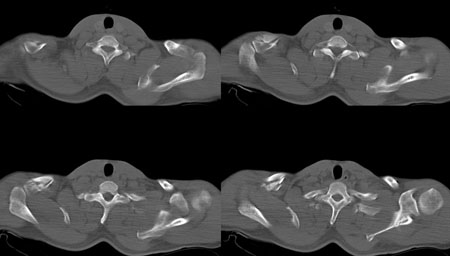

男,36岁  车祸伤及胸部。

右锁骨及左肩胛骨骨折,最后两幅图气管隆突下见结节灶,建议用纵隔窗除外血肿

右锁骨肩峰端粉碎骨折;左肩胛骨粉碎骨折。

再加上左侧第2后肋骨折。